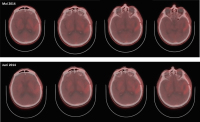

Abbildung 3: Follow-up-Imaging vom Februar 2014: MRT + KM, MRT FLAIR und pMRT, sowie FET-PET zeigen deutliche Hinweise für „Pseudoprogression“. Deutlich ausgeprägte KM-Aufnahme (MRT + KM), verminderte Perfusion in der pMRT und herabgesetzte Traceraufnahme im FET-PET im Vergleich zum Vorbefund (Tumorbereich mit Pfeil markiert)

Abbildung 4: Follow-up-Imaging vom Mai 2014: MRT + KM, MRT-FLAIR und pMRT, sowie FET-PET zeigen nach wie vor keine eindeutigen Hinweise auf Tumoraktivität. Vergleiche Abb. 2 und 3 (Tumorbereich mit Pfeil markiert)